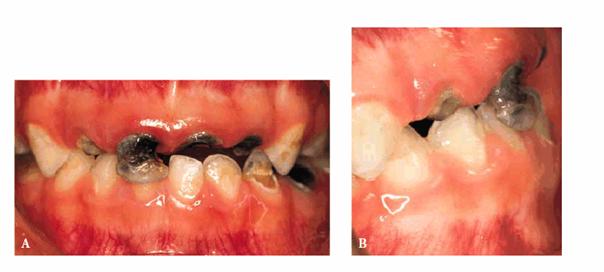

Approach

A male patient, 36 months old.

PROBLEM: He presented with rampant caries involving four maxillary

anterior teeth and caries in the lower arch. The parents hoped that the teeth

could be saved. Initial radiographs were taken (Figures 27-2A

and B

Figure 27-2A and B: Rampant caries involving the anterior teeth and the lower arch.

TREATMENT: Caries were removed, and endodontic treatment was performed.

Aluminum oxide posts were used. A rubber-base impression was made for

laboratory-processed full acrylic crowns (Figure 27-2C

Figure 27-2C: Crowns are seated with an acceptable result.

RESULT: Crowns were seated with an acceptable result. Figures 27-2A and 27-2D show the sharp contrast between

before and after treatment. The child was able to resume his usual activities

without discomfort or fear of future embarrassment.

Figure 27-2D: The radiograph shows the endodontic treatment performed and the restoration of the lower caries.